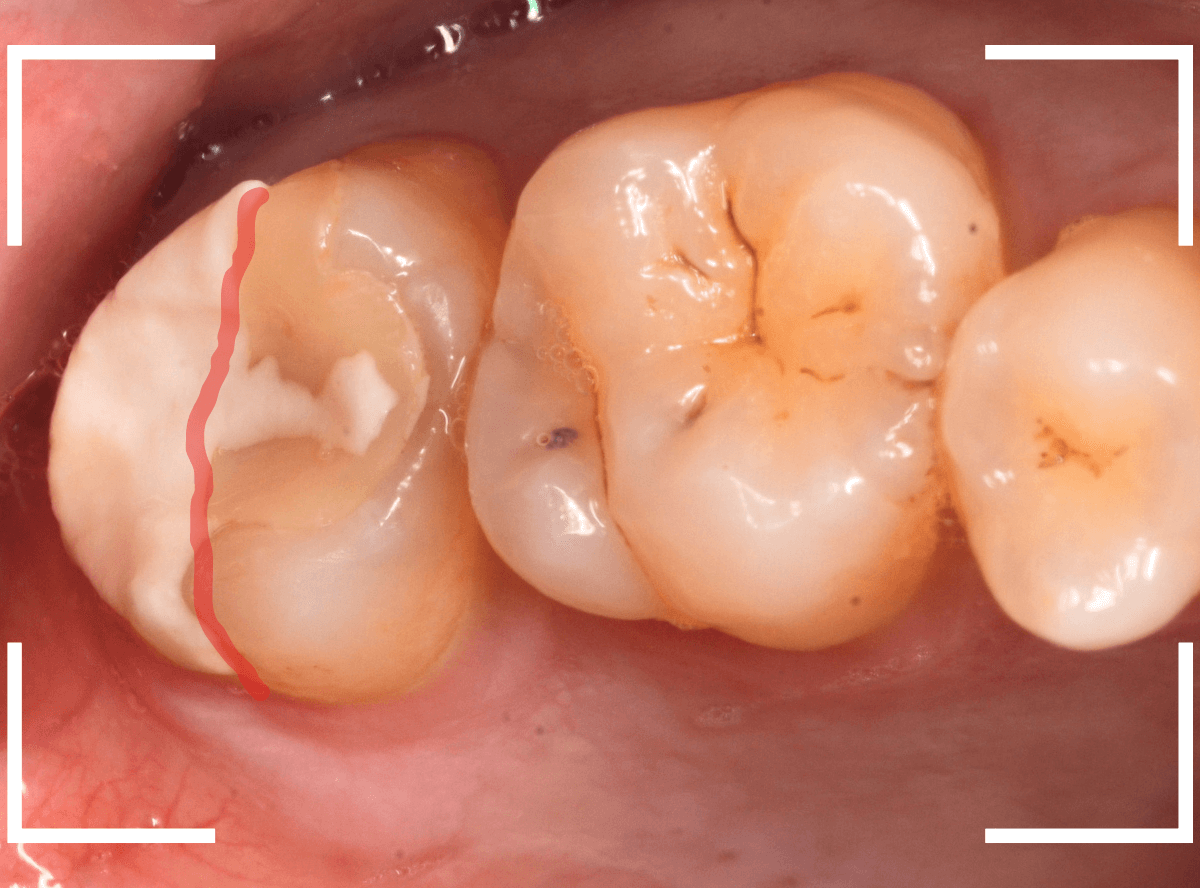

虫歯を治療して、セメントで歯を削った部分を封鎖した後、再修復を検討中で、半年以上来院されなかった患者さんです。

虫歯を治療して、セメントで封鎖した状態というのは、家でいえば、しっかりした屋根がない状態です。

今回は、セメントの一部がはがれる程度で済んでいましたが、虫歯が再発し、再治療、最終修復物の変更の可能性も出てきます。

治療再開後、セラミックの最終修復を希望されましたので、歯をトリミングし、型取りします。